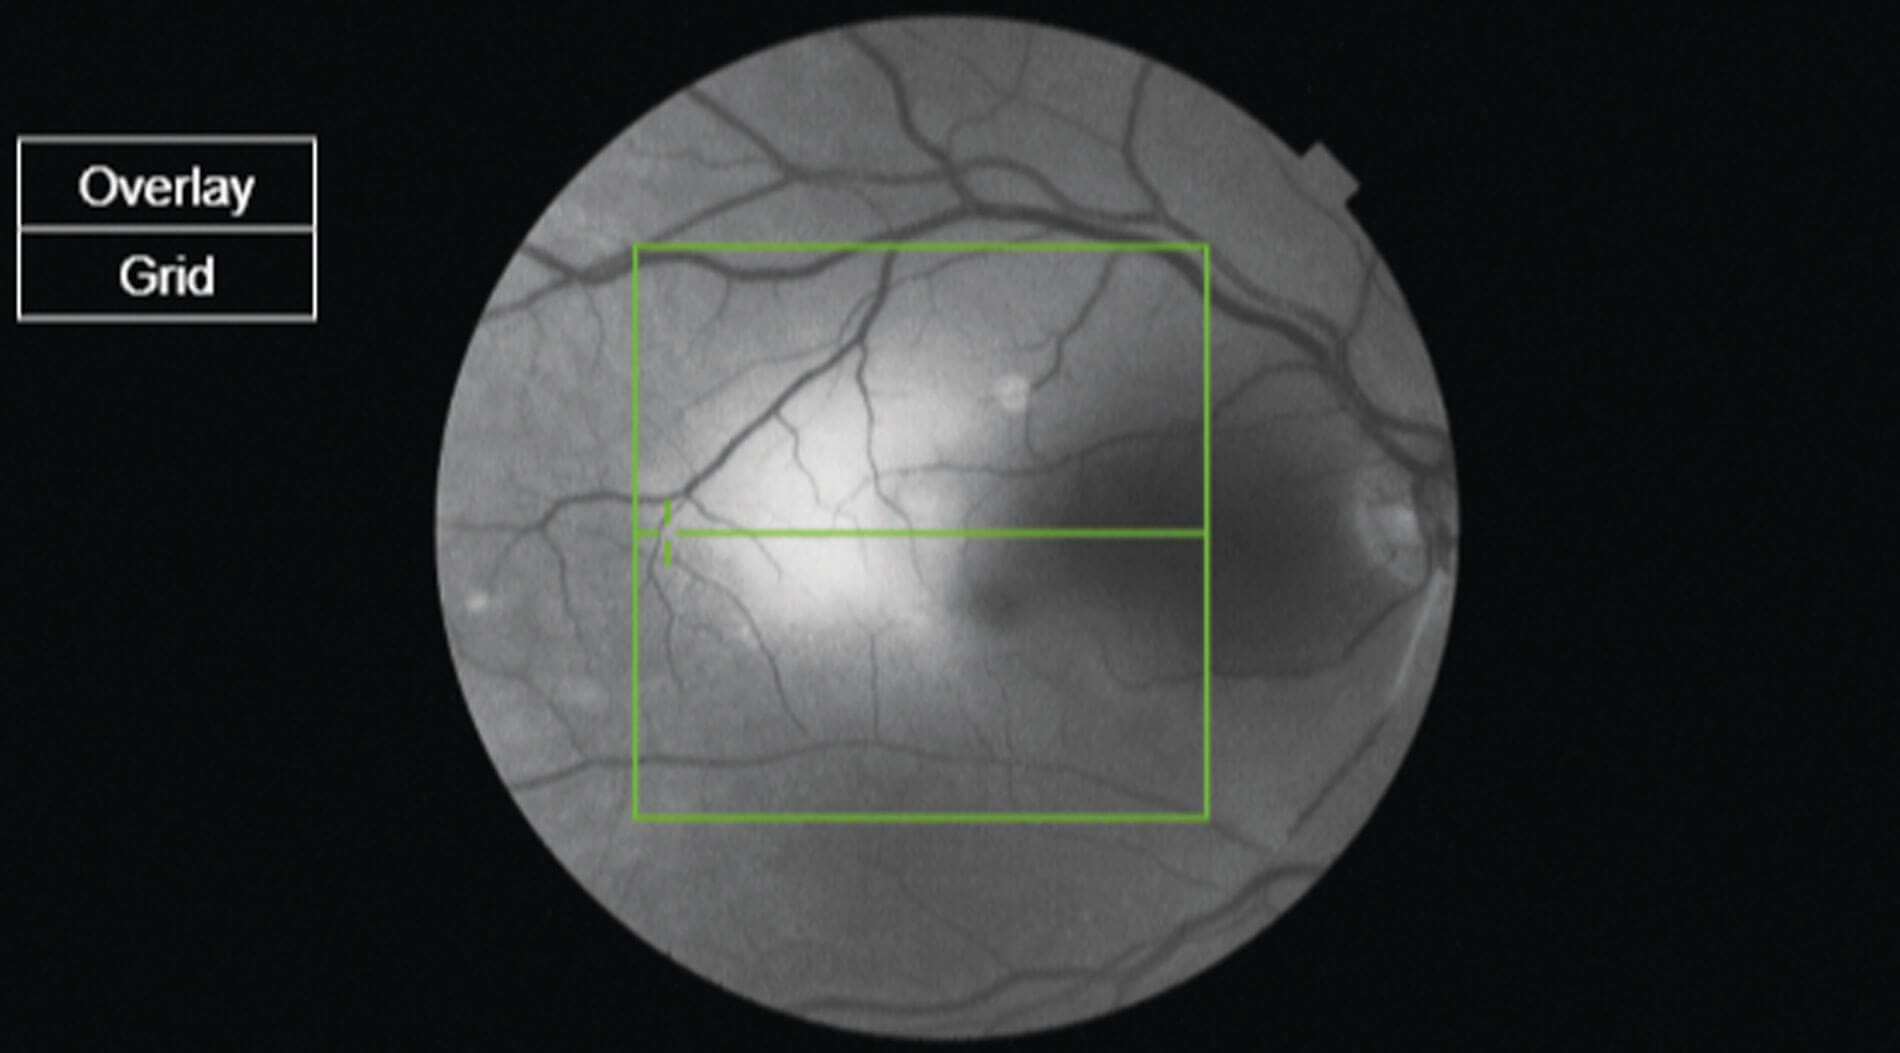

Figure 1: Image obtained on OCT scan showing right fundus showing widespread retinal oedema

sparing the cilioretinal artery territory and a large thrombus inferior temporally (arrow).

A 75-year-old gentleman attended the emergency eye department complaining of sudden painless loss of vision in the right eye for approximately two hours. He presented very early following the onset of his symptoms as he had a similar episode to his left eye few weeks ago and on that episode he was told that if this affects his right eye, he needs to present to the emergency eye clinic as soon as possible. At the emergency clinic, he was immediately triaged and identified as being at risk of CRAO. As such, he had bloods to exclude giant cell arteritis (full blood count, erythrocyte sedimentation rate and C-reactive protein) and was prioritised to be seen. On examination Right eye visual acuity was 1.46(LogMar). On fundoscopy he was found to have a pale ischaemic retina, confirmed on OCT scanning. He was also noted to have a thrombus as shown in Figure 1, which confirmed the diagnosis of CRAO. He was immediately treated with intravenous acetazolamide 500mg, oral acetazolamide 500mg, topical Cosopt, Iopidine and Xalatan, oral aspirin 300mg, ocular massage and rebreathing in a bag.

The article includes the patient’s fundus picture which shows a large embolus (not “thrombus” as stated) along the inferotemporal vascular arcade. Embolism originating from atherosclerotic plaques within the carotid artery or heart is the commonest cause of CRAO.1 Studies show that the most common location of occlusion of central retinal artery is more proximal, at the site of piercing the dural sheath of optic nerve or at the lamina cribrosa.2 The embolus in the fundus picture is more likely to cause a Branch Retinal Artery Occlusion (BRAO) than a CRAO. Lastly, a Fundus Fluorescein Angiogram would have shone a lot of light on the diagnosis and extent of ischaemia in both eyes.